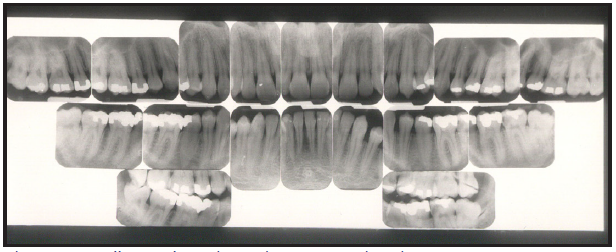

Bitewing examinations were introduced by Dr. Raper in 1925. Bitewing images focus on the clinical crowns of both the maxillary and mandibular teeth. Bitewings do not show the apices of the tooth and cannot be used to diagnose in this area. The greatest value of bitewing radiographic images is the detection of interproximal caries in the early stages of development, before it is clinically apparent. The arrows in Figure 2 indicate areas of interproximal caries. Bitewing images also reveal the size of the pulp chamber and the relative extent to which proximal caries have penetrated.

Figure 2 – Bitewing Images

Figure 2